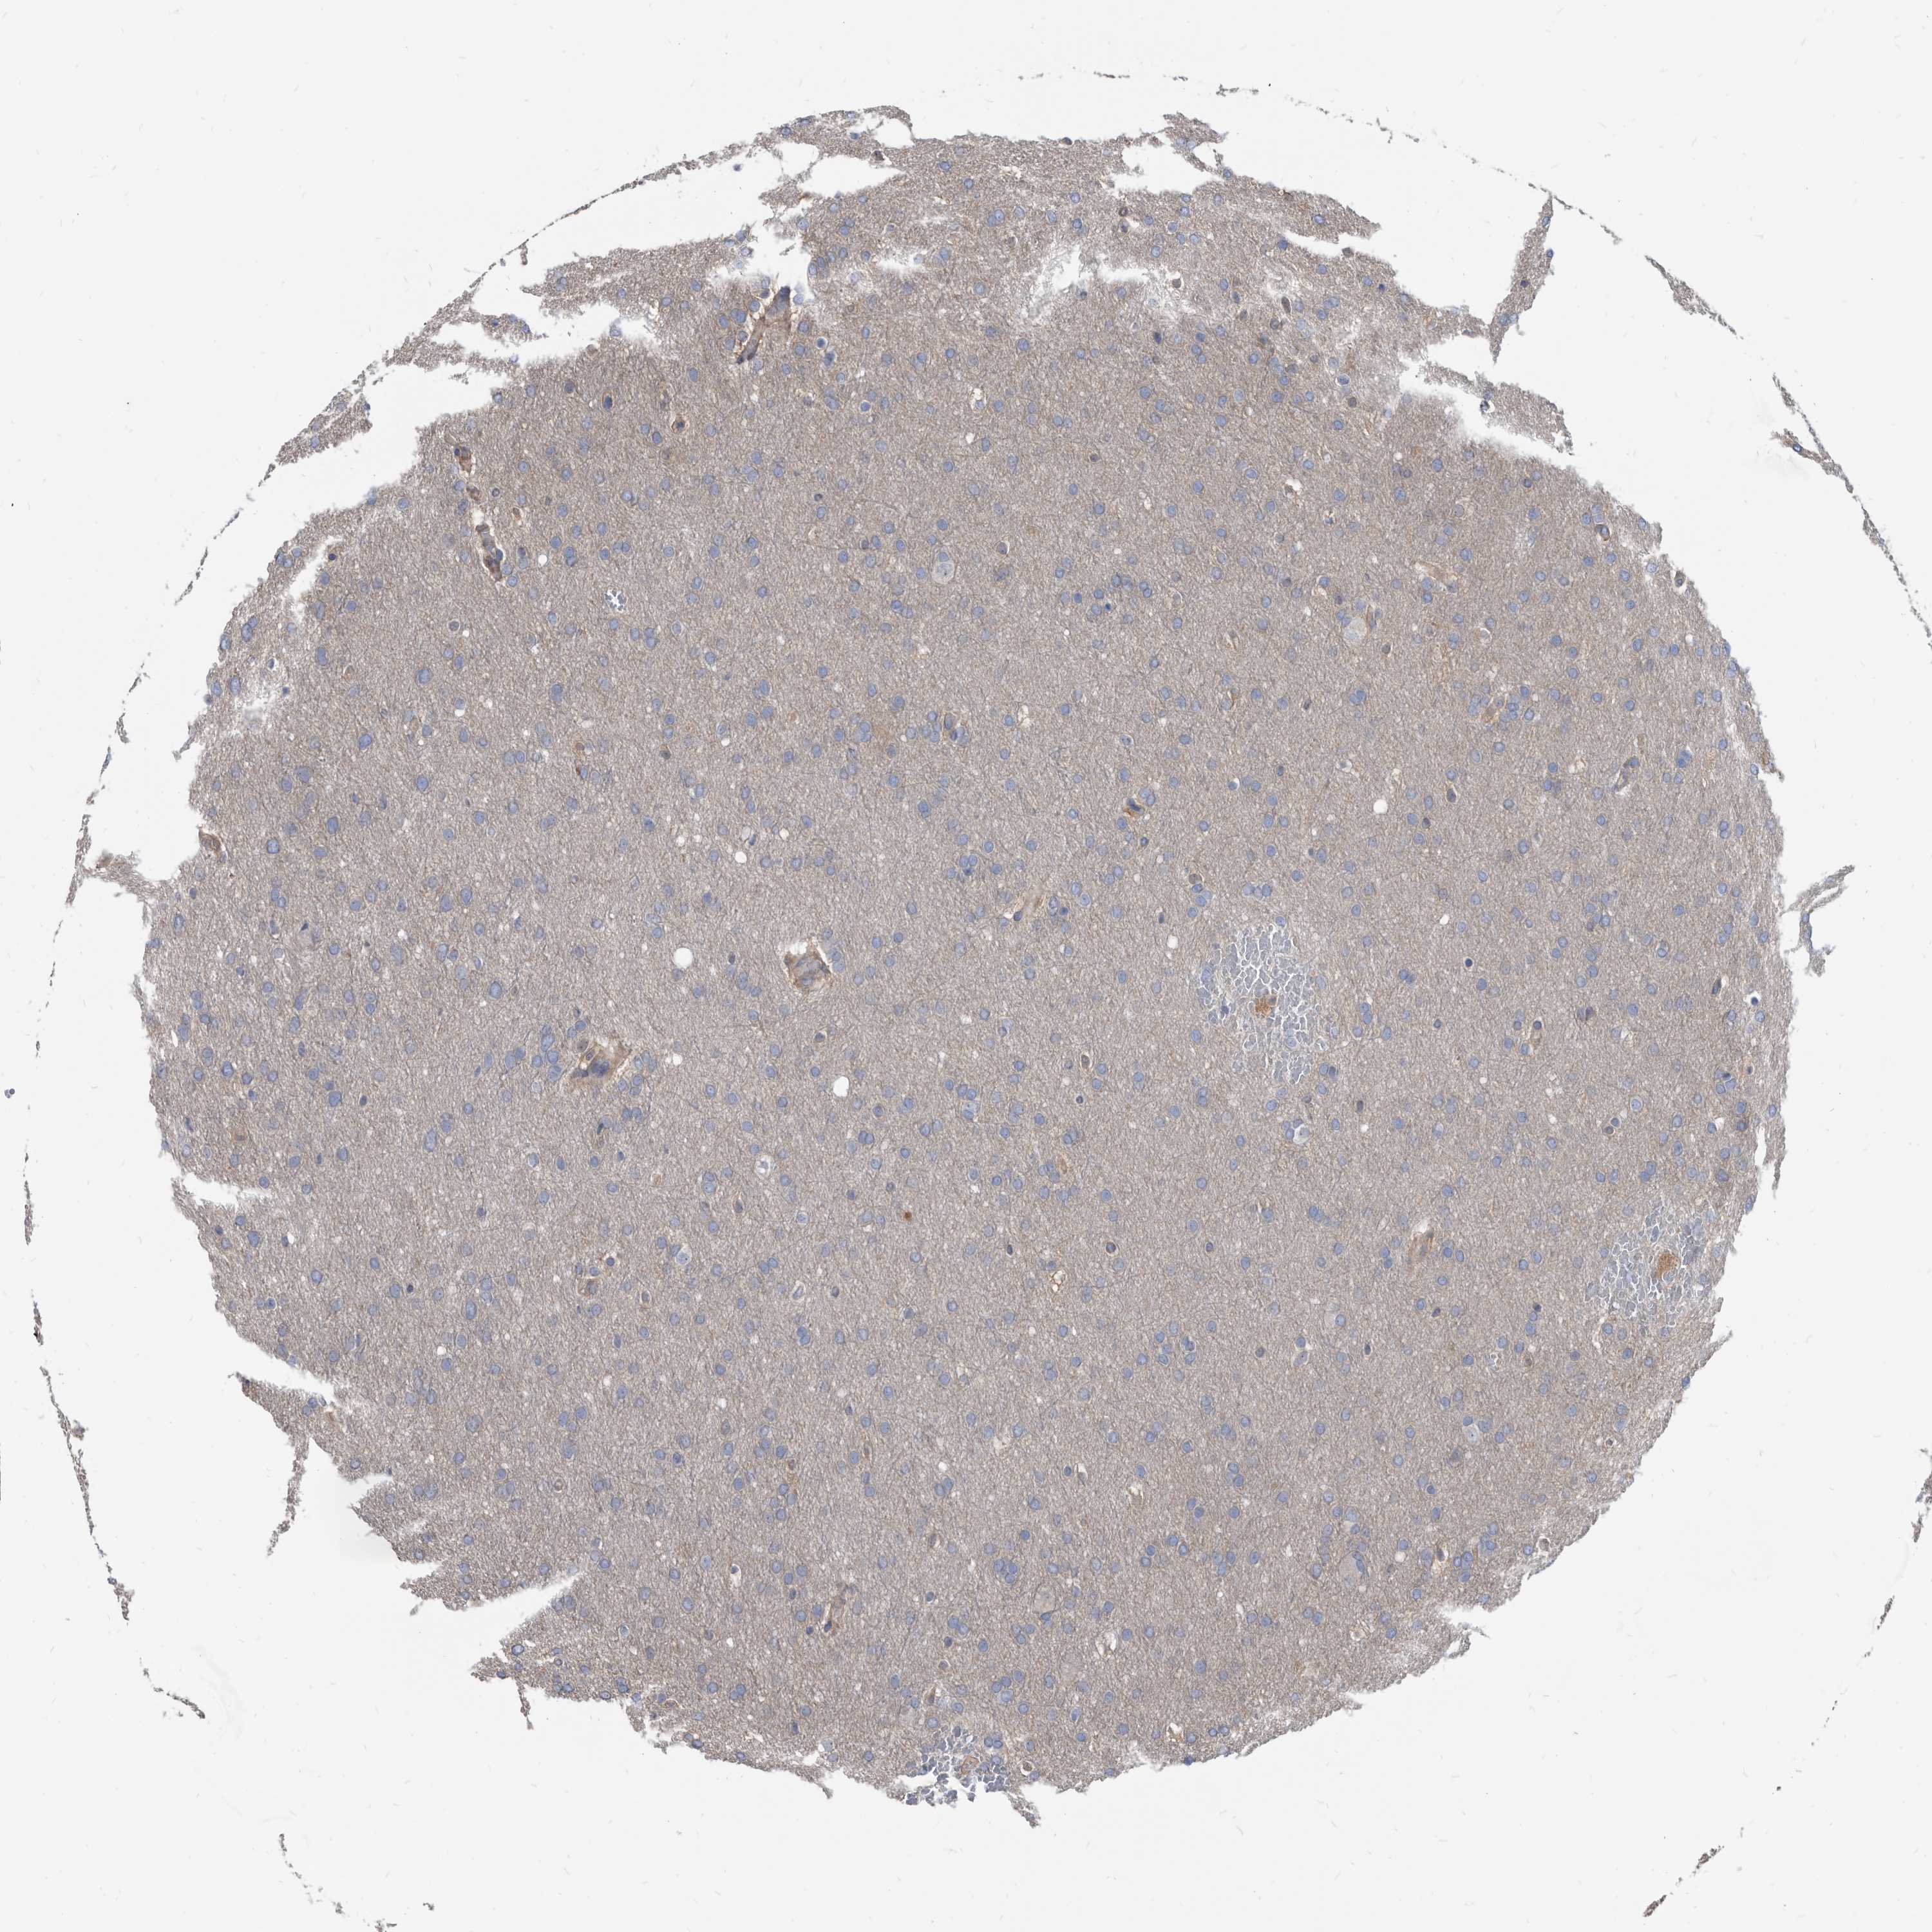

GLIOMA - Protein expressioni

A mouse-over function shows sample information and annotation data. Click on an image to view it in a full screen mode. Samples can be filtered based on level of antibody staining by selecting one or several of the following categories: high, medium, low and not detected. The assay and annotation is described here.

Note that samples used for immunohistochemistry by the Human Protein Atlas do not correspond to samples in the TCGA dataset.

Antibody stainingi

Antibody staining in the annotated cell types in the current human tissue is reported as not detected, low, medium, or high, based on conventional immunohistochemistry profiling in selected tissues. This score is based on the combination of the staining intensity and fraction of stained cells.

Each image is clickable and will lead to virtual microscopy that enables deeper exploration of all samples and also displays staining intensity scores, fraction scores and subcellular localization as well as patient and tissue information for each sample.

Antibody HPA029700

Antibody HPA029701

Antibody HPA029702

Antibody HPA029703

Staining

High

Medium

Low

Not detected

Intensity

Strong

Moderate

Weak

Negative

Quantity

>75%

75%-25%

<25%

None

Location

Nuclear

Cytoplasmic/membranous

Cytoplasmic/membranous,nuclear

Glioma, malignant, High grade

Glioma, malignant, Low grade

Glioblastoma, NOS